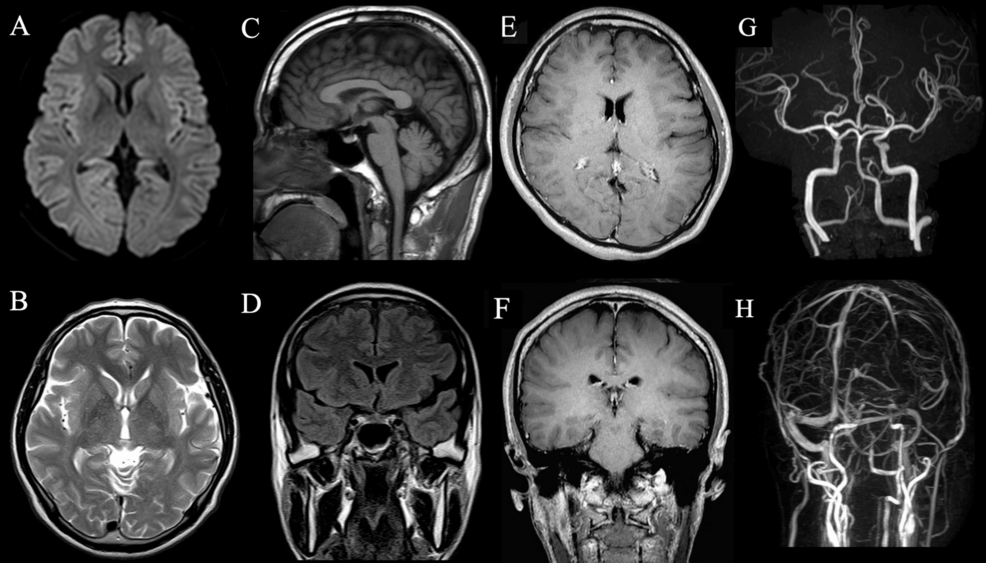

The case involved a patient who developed a headache immediately following a mild, unspecified infection. Neurological examination was initially normal, but subsequent analysis of cerebrospinal fluid (CSF) revealed mild pleocytosis, an elevated number of white blood cells indicating inflammation. This finding is crucial, as it suggests an inflammatory process within the central nervous system.

According to the report, “The patient’s headache was unrelenting and significantly impacted their daily activities.” Initial treatments proved ineffective, prompting further investigation. The CSF analysis revealed a white blood cell count of 12 cells/µL, slightly elevated but not indicative of a severe infection. Protein levels were normal, and bacterial cultures were negative, ruling out typical bacterial meningitis.